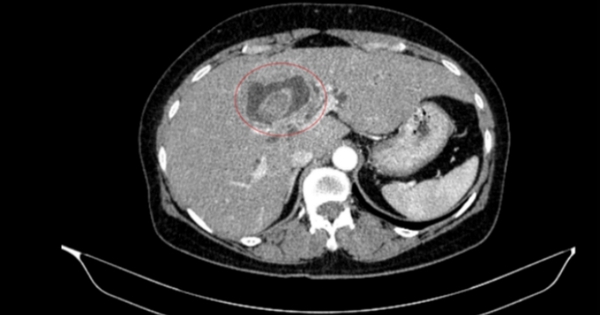

Bệnh nhân 59 tuổi nhập viện vì vàng da, ngứa kéo dài, được phát hiện đồng thời ung thư đại tràng phải và ung thư đường mật trong gan.